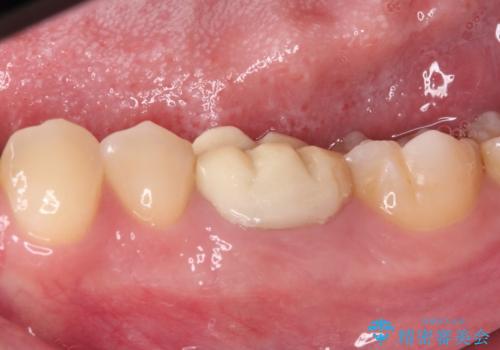

- 食事の度にクラウンにこびりつくとのことで来院された患者様です。

以前の医院では治療終了と言われたそうですが、即席で製作した仮歯が装着された状態でした。

患者様と相談し、根管治療を再度行った後、フルジルコニアクラウンにて補綴治療することとしました。